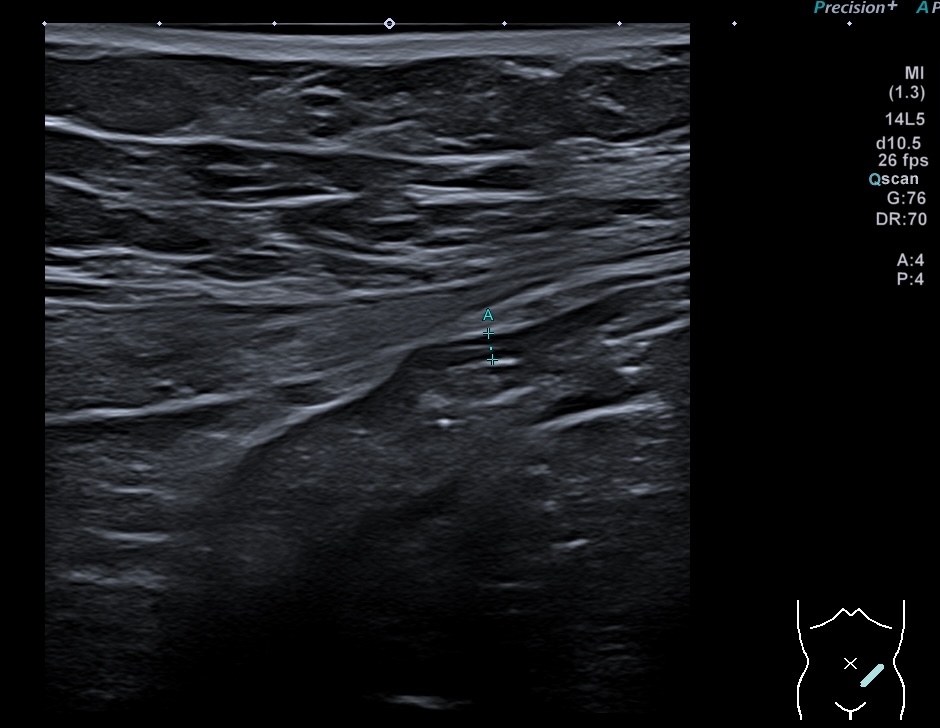

Echographie 22/12/2022

Epaississement considérable par endroit (10 ou 11 mm), disparition totale de la structure en couches, déformation de la surface avec ulcérations, déformation des contours, infiltration de la graisse, hyperactivité Doppler

Le Score de Milan (MUC) est à 17.4

Les images échographiques correspondent parfaitement aux images endoscopiques, et sont finalement beaucoup plus précises que les images scanographiques.

Endoscopie Mayo 3 UCESI 7/8 ulcères creusants

L’histologie confirme une RCH grave sans surinfection par le CMV.